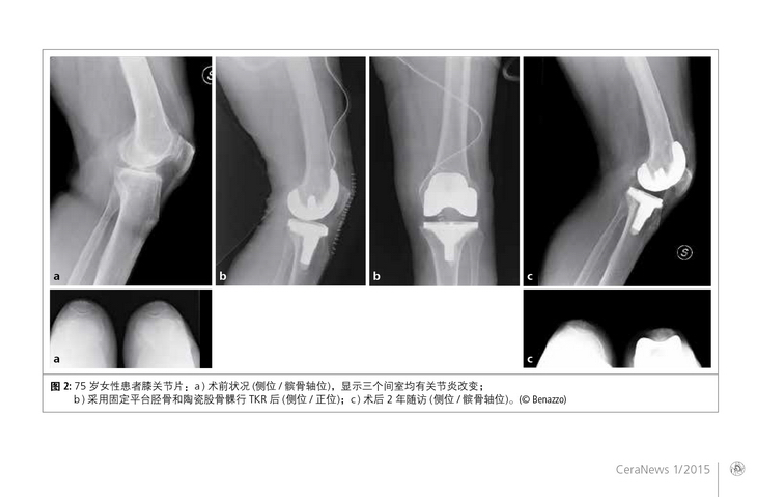

第一作者:Benazzo F